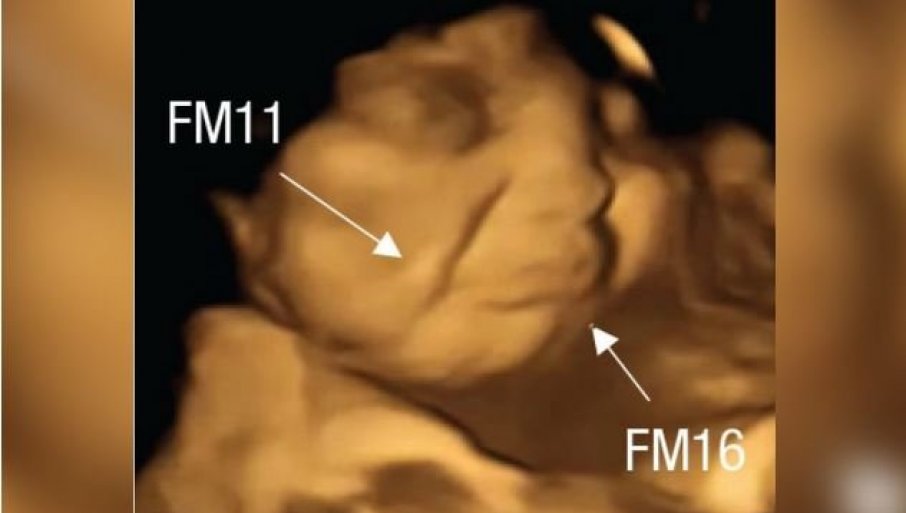

Foto: FETAP Study/Fetal and Neonatal Research Lab/Durham University

Reakcija posle kapsule kelja

Tim naučnika je nakon pregleda obavljao analizu svakog snimljenog kadra i posmatrao izraze lica fetusa, uključujući i kombinacije grimasa koje su izgledale kao plač ili smejanje. Napravljeno je više od 180 ultrazvučnih snimaka na 99 fetusa, koji su skenirani u 32. i 36. nedelji trudnoće.

Plačni izrazi lica bili su dva puta češći kada su majke konzumirale kapsule sa keljom u poređenju sa fetusima čije su majke uzimale kapsule sa šargarepom ili nisu uopšte uzimale kapsule. U slučaju kapsula sa ukusom šargarepe, lica nerođenih beba su često dobijala izraz osmehivanja.

Reakcija posle šargarepe